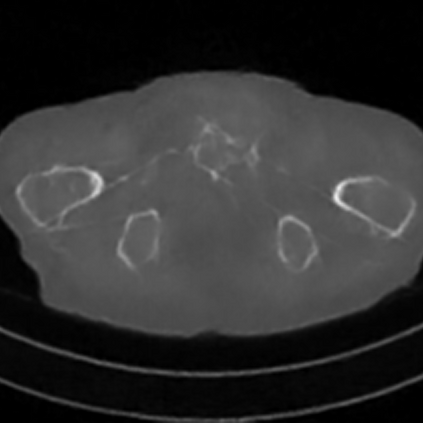

Sparse-view computed tomography (CT) -- using a small number of projections for tomographic reconstruction -- enables much lower radiation dose to patients and accelerated data acquisition. The reconstructed images, however, suffer from strong artifacts, greatly limiting their diagnostic value. Current trends for sparse-view CT turn to the raw data for better information recovery. The resultant dual-domain methods, nonetheless, suffer from secondary artifacts, especially in ultra-sparse view scenarios, and their generalization to other scanners/protocols is greatly limited. A crucial question arises: have the image post-processing methods reached the limit? Our answer is not yet. In this paper, we stick to image post-processing methods due to great flexibility and propose global representation (GloRe) distillation framework for sparse-view CT, termed GloReDi. First, we propose to learn GloRe with Fourier convolution, so each element in GloRe has an image-wide receptive field. Second, unlike methods that only use the full-view images for supervision, we propose to distill GloRe from intermediate-view reconstructed images that are readily available but not explored in previous literature. The success of GloRe distillation is attributed to two key components: representation directional distillation to align the GloRe directions, and band-pass-specific contrastive distillation to gain clinically important details. Extensive experiments demonstrate the superiority of the proposed GloReDi over the state-of-the-art methods, including dual-domain ones. The source code is available at https://github.com/longzilicart/GloReDi.